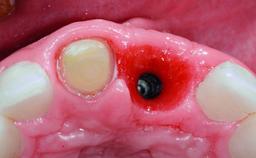

A 32-year-old female Caucasian patient with a compromised maxillary right central incisor was referred to us by a general dentist. Her chief complaints were discomfort and mobility of tooth 11 with unsatisfactory esthetics due to discoloration. The patient reported a previous trauma, some years earlier, as the origin of pathology on the afflicted tooth. Anamnesis was negative for any other dental or periodontal pathology in the remaining dentition. The patient did not take any medication and reported to be a light smoker (5–10 cigs/day). She had high esthetic expectations of her treatment. The extraoral examination revealed a high smile line with full exposure of her maxillary teeth and surrounding soft tissue in the area between the second premolars.

Placement Protocol Early or late implant placement

Bone Volume Deficient horizontally, requiring prior grafting